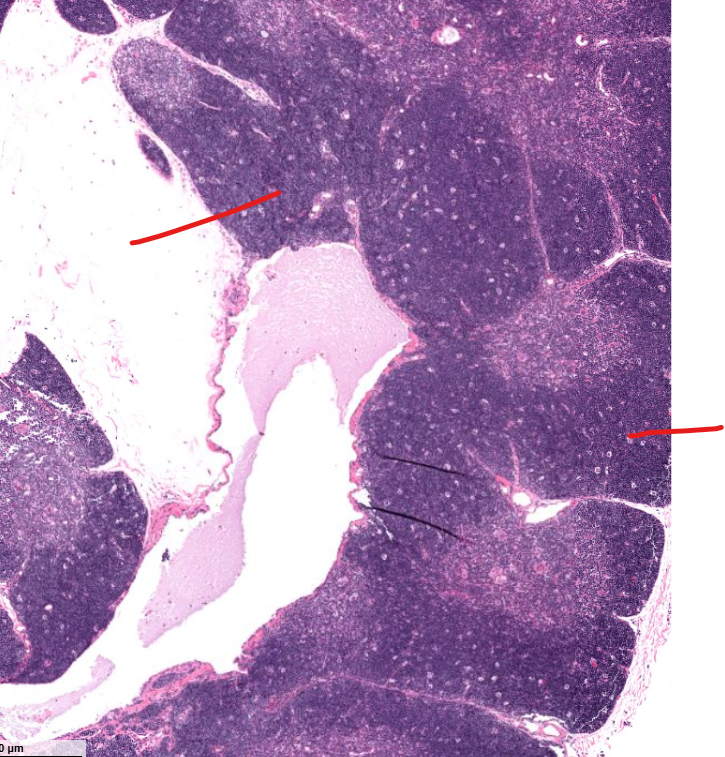

cortex of the thymus

contains t cells

macrophage (shown in the thymus)

medulla of the thymus